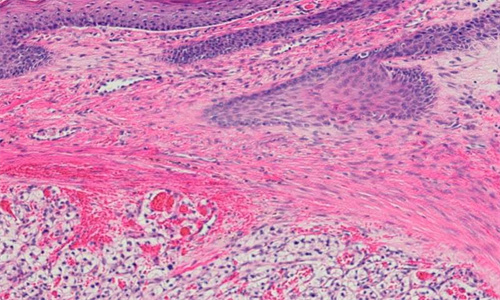

巴斯克地区大学(UPV/EHU)的一项研究,使用博弈论来确定细胞异质性较低的肿瘤更具侵袭性。数学、组织病理学和基因组学共同证实,更具侵袭性的透明细胞肾细胞癌表现出低水平的瘤内异质性,即它们包含较少的不同细胞类型。